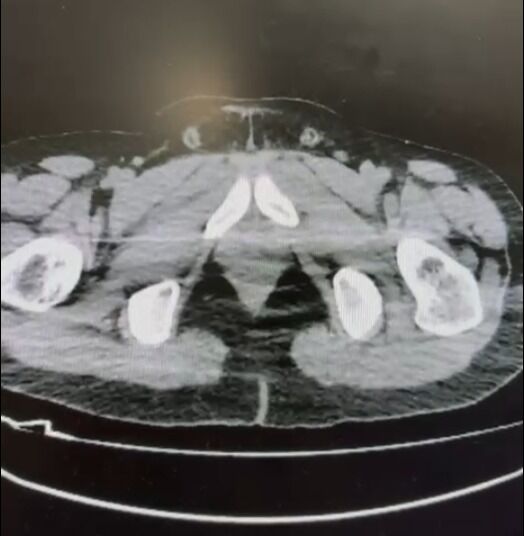

Ekipler, S.B. ve O.R. isimli şüphelilerin “yutma yöntemi” ile kente uyuşturucu madde getireceği bilgisi üzerine harekete geçti. Şüphelilerin konutlarında ve kullandıkları araçlarda yapılan aramalarda

• 101 kapsül halinde 722 gram metamfetamin,